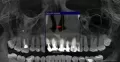

В зубе имеется хронический воспалительный процесс, и методы лечения были, мягко говоря, некорректными. Обратитесь на очный приём, необходим прицельный снимок для оценки возможности безоператорного лечения кисты, в противном случае, резекция верхушки корня будет правильной альтернативой.